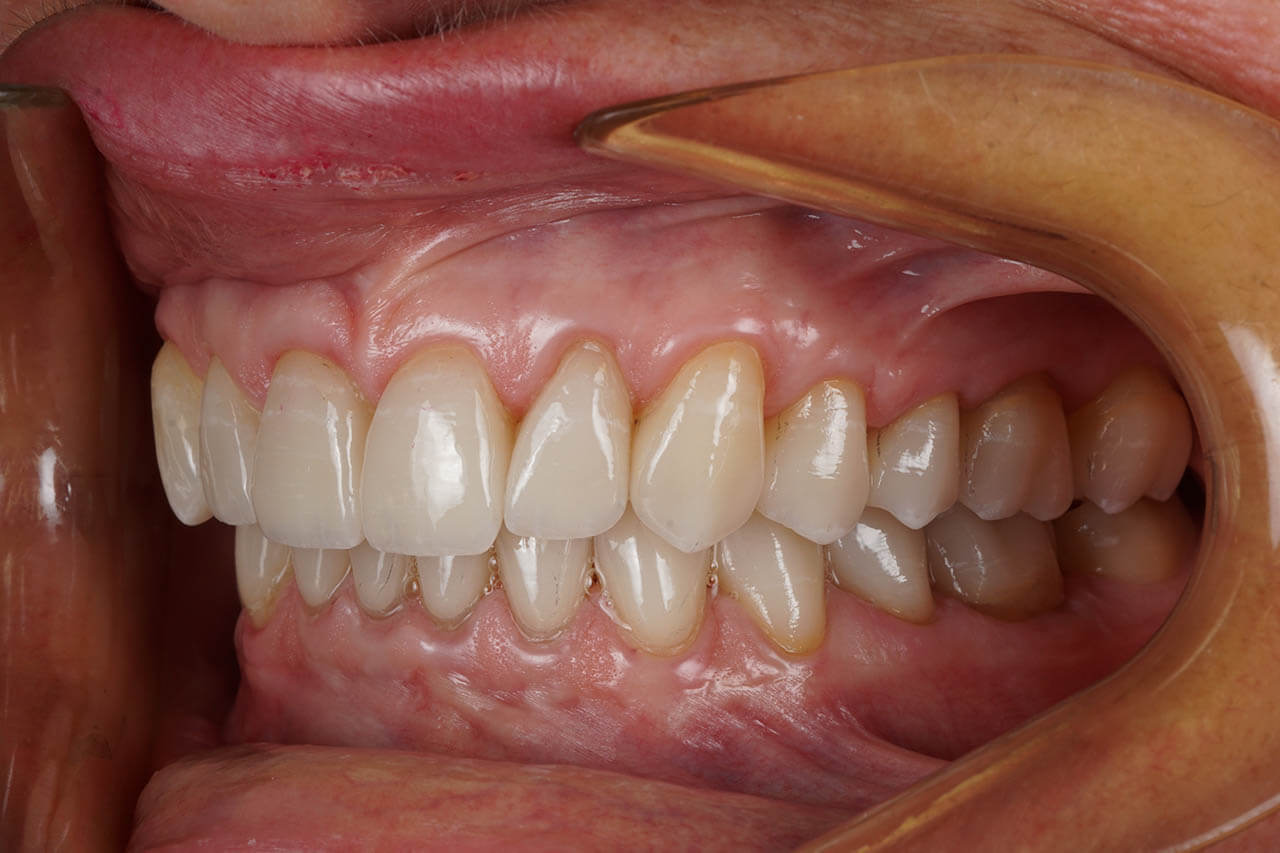

Dental prosthetics deals with filling gaps in the dentition and reconstructing damaged teeth. It is a good choice for anyone who in the past did not properly care for their teeth and as a result could not maintain their natural dentition or lost teeth due to illness or an unfortunate event. A properly chosen partial or full denture allows for the recovery of an aesthetic smile, good well-being, and self-confidence. Prosthetics at the Z Wieży clinic in Władysławowo offers you a wide range of modern prosthetic solutions, from which everyone can choose something tailored to their needs and expectations regarding the final result. Our experienced, highly qualified doctors are ready to provide assistance and good advice. To ensure the highest quality and aesthetics of restorations, we have for years cooperated with a renowned prosthetic laboratory.

Types of prosthetic restorations used at the Z Wieży clinic:

• Porcelain and all-ceramic prosthetic crowns;

• Acrylic and zirconia crowns;

• Dental bridges and dentures.

Our prosthetic work